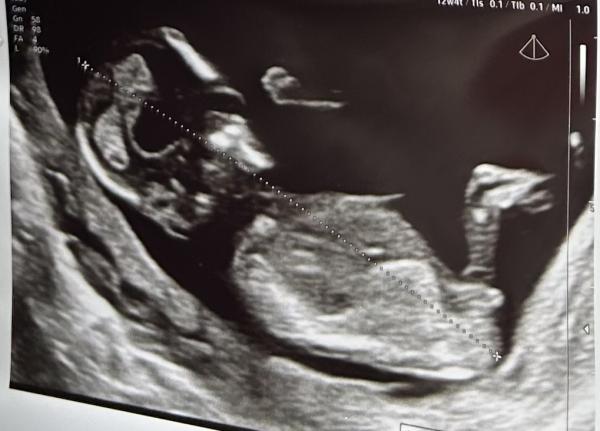

Hallo zusammen, ich bin ganz neugierig darauf zu erfahren welches Geschlecht unser zweites Wunder hat 😊 Meine Ärztin sagt der NUB ist wohl noch sehr neutral weder nach oben noch nach unten gerichtet.. ich weiß nur nicht ob sie einfach noch nicht ihre Tendenz verraten möchte😄   Was denkt ihr von den Bildern her?  Mädchen oder Junge?

Bild zu Nun - Theorie / Geschlecht? - Schwanger - wer noch? Rund um die Schwangerschaft

Ich sage Mädchen :)